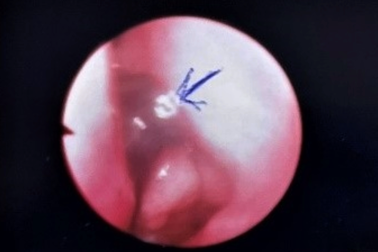

Gắp con vắt trong mắt bé trai 8 tuổiMới đây, một phòng khám tại huyện Quỳ Hợp, tỉnh Nghệ An gắp thành công con vắt nằm trong mắt bé trai 8 tuổi.